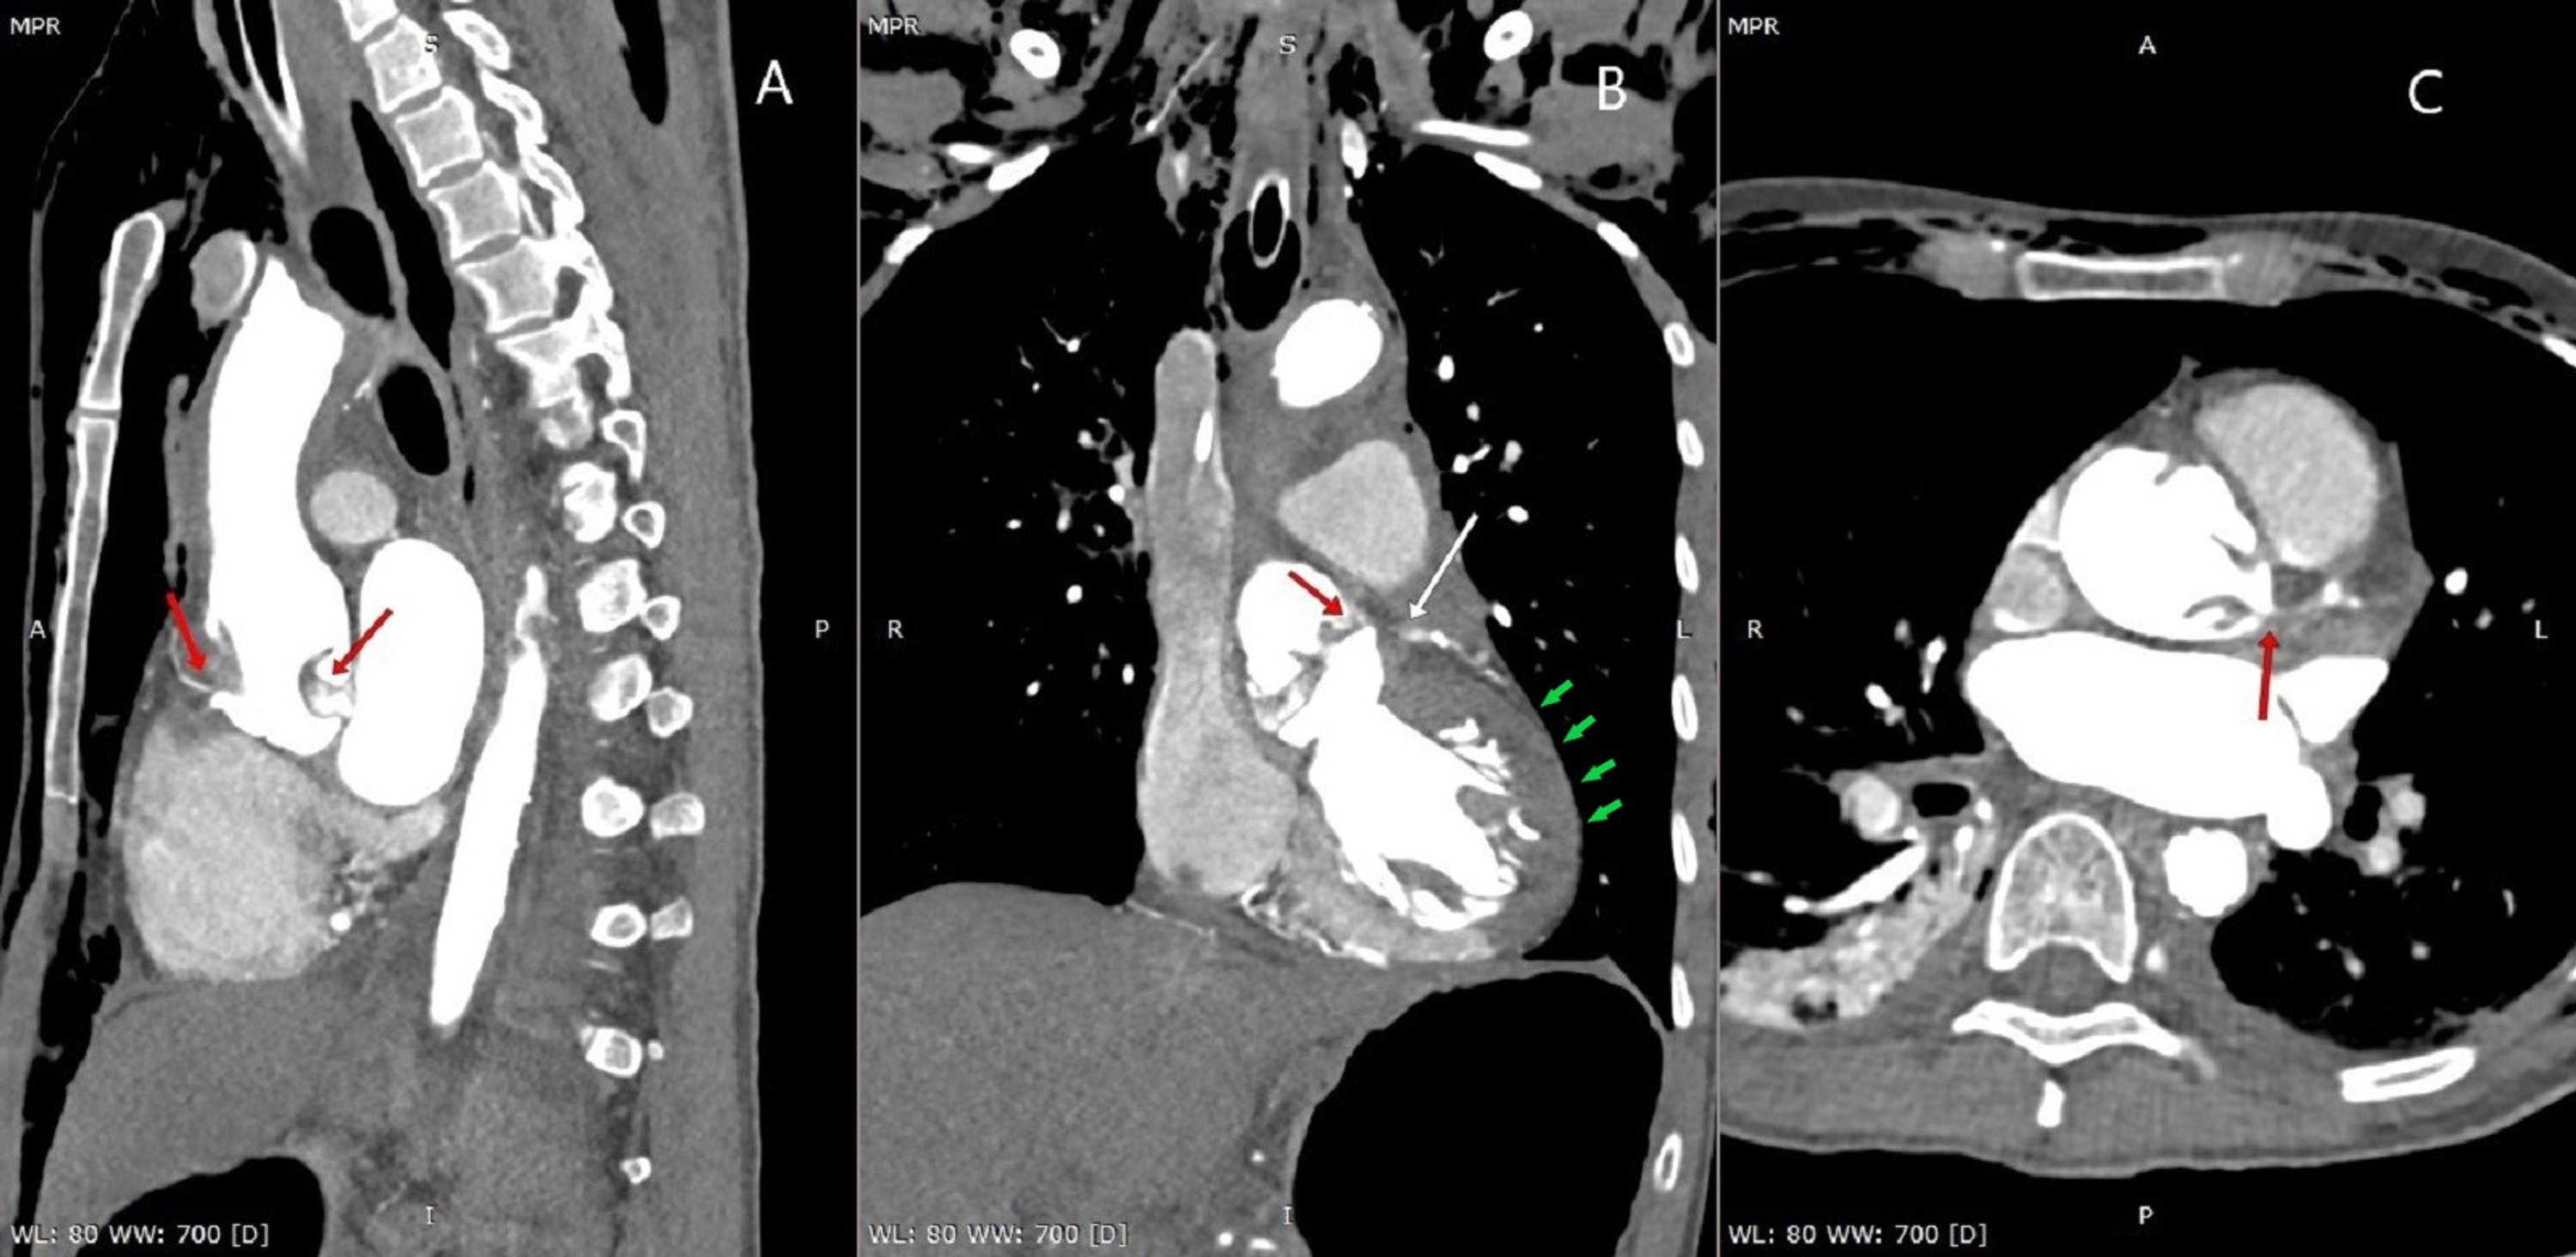

Dissection flap in the descending aorta with leftsided pleural Flap Dissection Concern about extension of the dissection. There are several indications to intervene: We sometimes need to intervene when patients present with artery dissection. This will result in not enough blood supply to that organ. Concern about an aneurysm forming around the dissection. Diagnosis is by imaging tests (eg, transesophageal echocardiography, ct angiography, mri, contrast aortography). A dissection flap may obstruct. Flap Dissection.

Aortic dissection. Intimal flap (red arrow) is seen in the dilated Flap Dissection Concern about an aneurysm forming around the dissection. Concern about extension of the dissection. Diagnosis is by imaging tests (eg, transesophageal echocardiography, ct angiography, mri, contrast aortography). A thin and often highly mobile dissection flap favors an acute process, whereas a thicker or immobile dissection flap favors a subacute or chronic process, but clinical correlation is needed and nearly all. Flap Dissection.